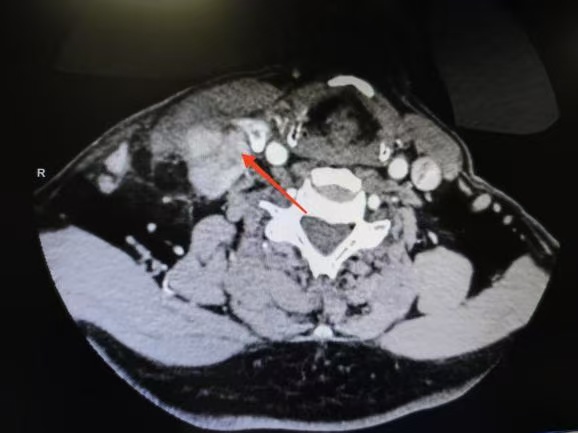

CT箭頭所示:側(cè)頸區(qū)轉(zhuǎn)移淋巴結(jié)